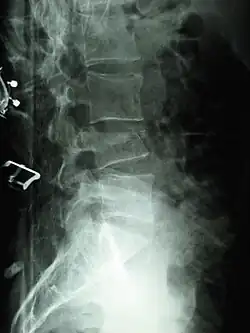

Compression fracture of the fourth lumbar vertebra post falling from a height. -